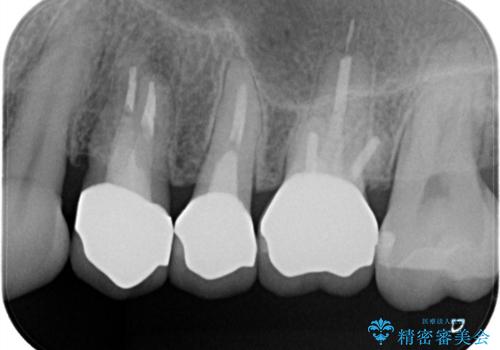

【オールセラミッククラウン】プラスチックの被せ物が壊れた。

- 以前他院で治療した被せ物が壊れたことを主訴に来院されました。

強度に優れたオールセラミッククラウンにて治療を行なっております。

3歯同時に治療を行うこと来院回数は4回で終了しています。